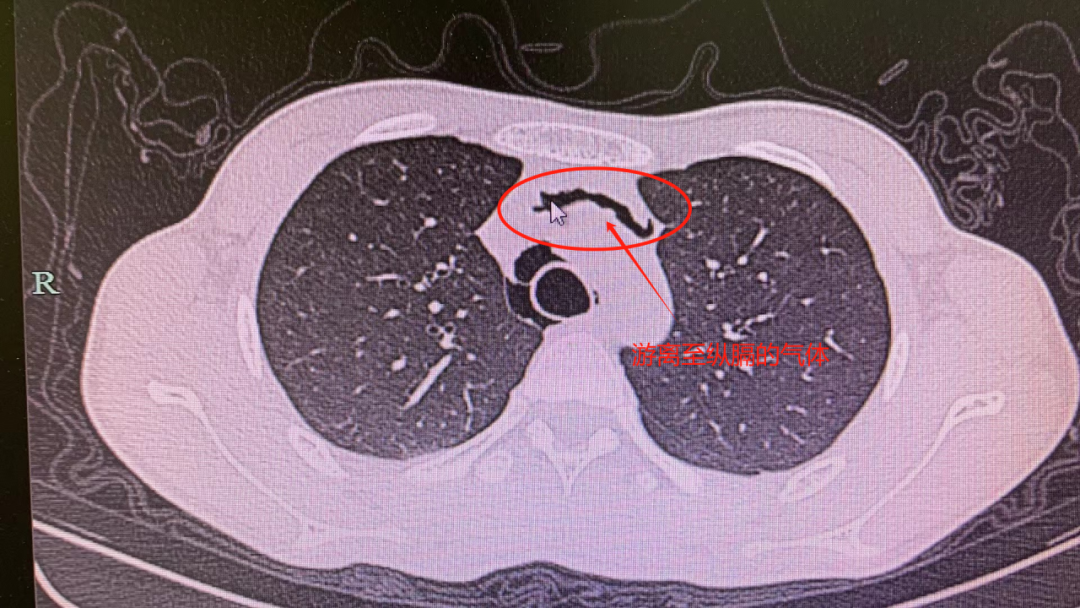

据东东妈妈表示,东东咳嗽一直很严重,入院当天甚至还出现了胸痛、精神萎靡不振的症状,急得家长赶紧将孩子送往浙大四院。经急诊医生迅速判断,东东这是因反复剧烈咳嗽导致的纵膈气肿,也就是俗话说的把肺咳「破」了。

「从肺里破出来的气体进入到纵膈的间隙里面,形成纵膈气肿,导致孩子胸痛,脖子有紧绷感,吃东西、咽口水也痛得厉害。」浙大四院心胸外科俞江灏医生表示。

纵膈气肿是指空气从肺部、气管或食道渗漏进入纵膈胸膜内结缔组织间隙之间,导致纵膈腔内出现游离空气。其症状与纵膈气肿发生的速度、积气量等相关。常见的症状为胸痛、呼吸困难和颈部的皮下气肿,医学上称之为「纵膈气肿三联征」。